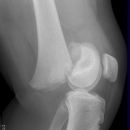

Kniegelenk